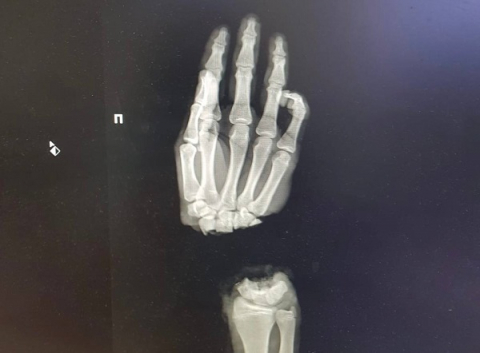

Врачи ПИМУ спасли отрубленную кисть руки 16-летнему подростку

Врачам Университетской клиники ПИМУ в Нижнем Новгороде удалось сохранить отрубленную кисть руки 16-летнему пациенту.

Юноша был доставлен в столицу Приволжья 1 марта из Коврова Владимирской области. Он случайно отрубил себе правую кисть, когда колол дрова. В тот же день нижегородские хирурги провели операцию по реимплантации конечности.

На данный момент подросток находится в обычном отделении, его состояние оценивается как стабильное. В ближайшее время пациенту предстоит еще несколько оперативных вмешательств, однако уже сейчас кровоснабжение руки восстановлено.

Кстати, в июле 2022 года с похожей травмой в ПИМУ доставили 5-летний ребенок. Спустя 8 месяцев конечность прижилась и двигается. Операции продолжаются.

Фото: ПИМУ